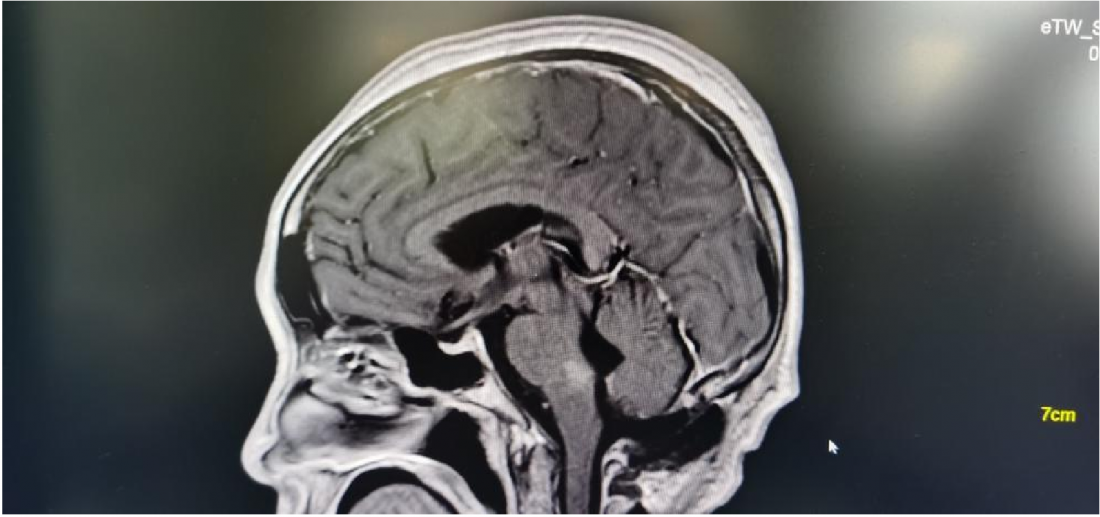

MR显示桥脑右侧高信号影,肿瘤位于四脑室界沟上方之桥脑部分,邻近面丘及动眼神经核,因此患者出现面瘫。

肿瘤位于桥脑与延髓交界处

面神经丘受压明显

术后MR: